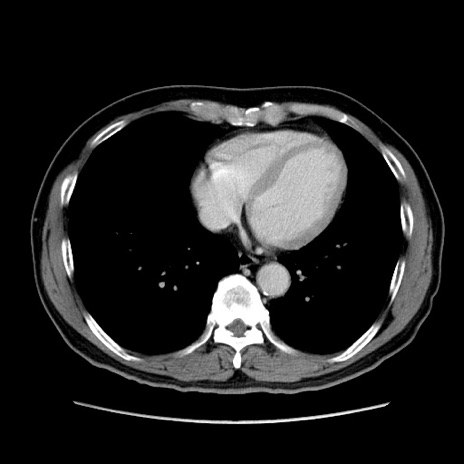

症例34(横断像)

【症例】60歳代 男性

【主訴】右鼠径部膨隆

【現病歴】1年程前より右鼠径部膨隆あり。自己にて還納可能だったため放置していた。3時間前より右鼠径部の脱出を認め、還納困難となり受診。

【既往歴】高血圧

【身体所見】右鼠径部に小児頭大の膨隆あり。弾性硬であり、用手還納は困難。左鼠径部にも膨隆を認める。脱出はなし。

【データ】WBC 15500、CRP 測定なし